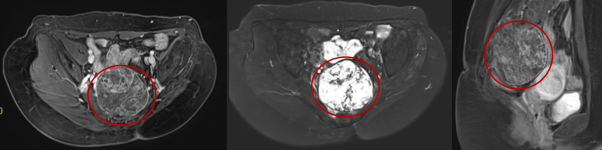

患者王**,女性,52岁,黎族,诊断:骶尾部脊索瘤。治疗前评估:MR-骶2-4椎体部分骨质破坏,相应平面见大小约8.8x7.1cm(S6,I57)混杂T1、混杂长T2肿块影,向盆腔内生长,局部侵及骶管,边界尚清;病灶约270度的范围内紧临结直肠。

2023年3月(碳)离子治疗前核磁检查,红圈内为肿瘤

2023年3月(碳)离子治疗前核磁检查,红圈内为肿瘤

治疗前肿瘤8.8×7.1cm,左图为MRI的T1轴位,中图为T2轴位,右图为T1矢状位